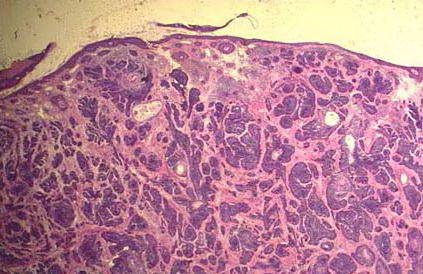

Bacillary angiomatosis = الورام الوعائي العصوي BACILLARY ANGIOMATOSIS Epidemiology BA is most commonly seen in patients with acquired immunodeficiency syndrome (AIDS) and a CD4 count less than 50 cells/mm3, with an incidence of 1.2 cases per 1000 at-risk patients Patients with other forms of immunosuppression, including patients with leukemia and recipients of organ […]